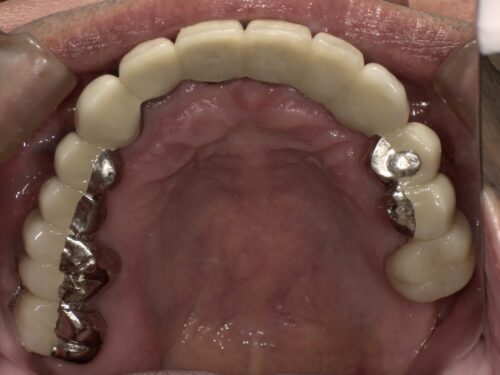

治療後の写真です。

前歯はブリッジとよばれる治療法で治しました。

奥歯でもしっかり噛めるようにすることで前歯にかかる負担を軽減しています。

歯一本一本だとグラグラしてしまうような状態でも、

ブリッジといってかぶせ物でつなぐことで全体として強度が上がるようにしています。

下の奥歯はインプラントを入れることで噛める範囲を増やしています。

お口の全体を使って噛むことは、

一部の歯に負担がかかることを防ぎ、

歯を長持ちさせることにつながります。